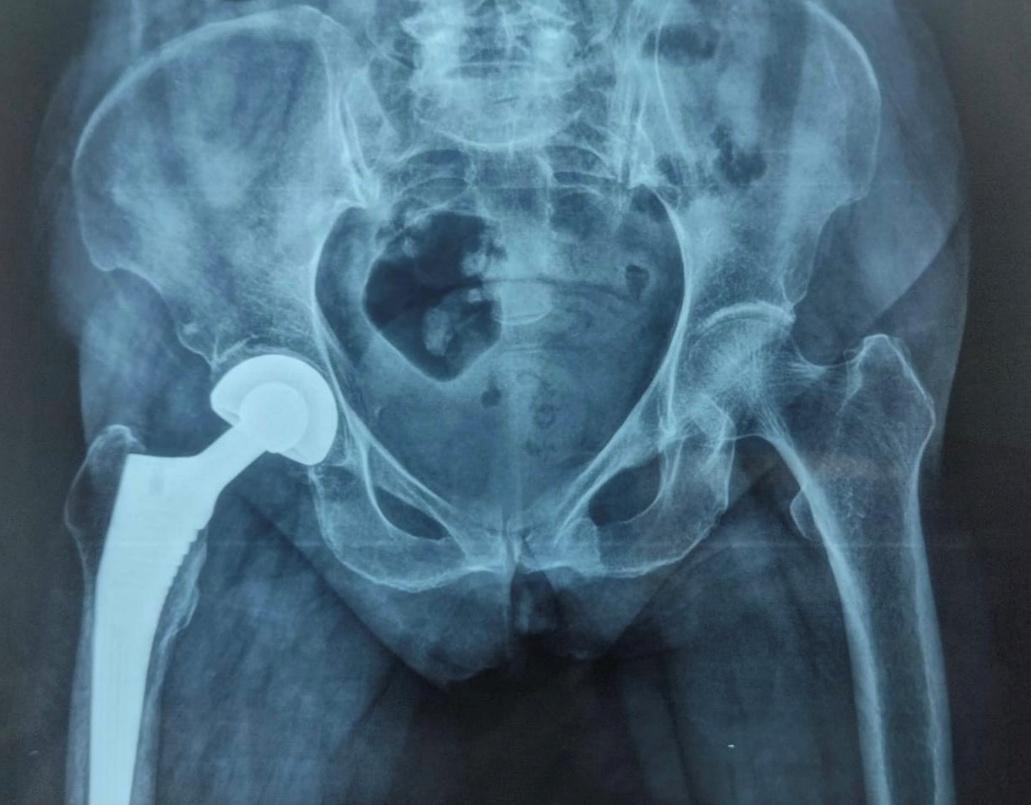

Surgery was performed under spinal anaesthesia using the modified lateral (Hardinge) approach. After femoral head extraction and canal preparation, a press-fit hydroxyapatite-coated femoral stem and modular bipolar head were implanted. Intraoperative findings, blood loss, implant size, and complications were recorded. A typical postoperative radiograph at nine months is shown in Figure 2.

Radiographic evaluations throughout follow-up demonstrated satisfactory implant alignment in all patients. Mean stem subsidence was minimal at 0.8 ± 0.4 mm, and no radiographic signs of loosening were observed. Only one patient developed Brooker Grade I heterotopic ossification.